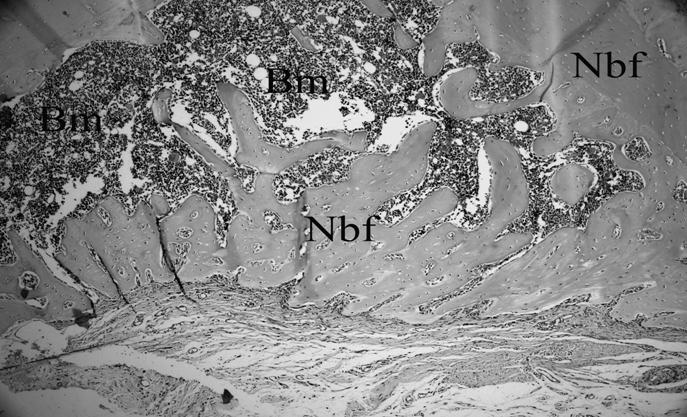

Figure 4

The histological view of the defect which is nearly filled with newly formed bone in the control groups which had received four week of HBOT (H&E×200) (Nbf; New bone formation, Bm; Bone marrow).

In groups which received HBOT, overall bone healing pattern was similar to non-HBO groups. However, from a subjective point of view, new bone formation was occupying larger areas which were previously filled by cartilage and fibrous connective tissues in groups which did not receive HBOT. At one week, there was no prominent inflammatory cell reaction in any of the three groups. Loose connective tissue and new bone trabeculae were found together with small islands of isolated cartilage tissue and abundant new vessels in the control group and around the bone grafts (Figure 1b, 1c). At two weeks, no cartilage or necrotic tissue formation was observed in the control group. Moreover, most of defects were already filled with newly formed bone. Similar observations were made in the groups in which the bone grafts and HBOT were used together. There were also prominent new vessel formations within the connective tissue surrounding the graft particles (Figure 1d). At four weeks, nearly all of the fibrous tissue was replaced by the newly formed bone in the control group. In β - TCP + HBOT group, there was some areas of residual graft particles surrounded mainly by a combination of mature and immature bone. Smaller areas containing graft particles were also present in CPCBB + HBOT group, however, the healing of defects in this group were close to that of the control group (Figure 2, 3 and 4).